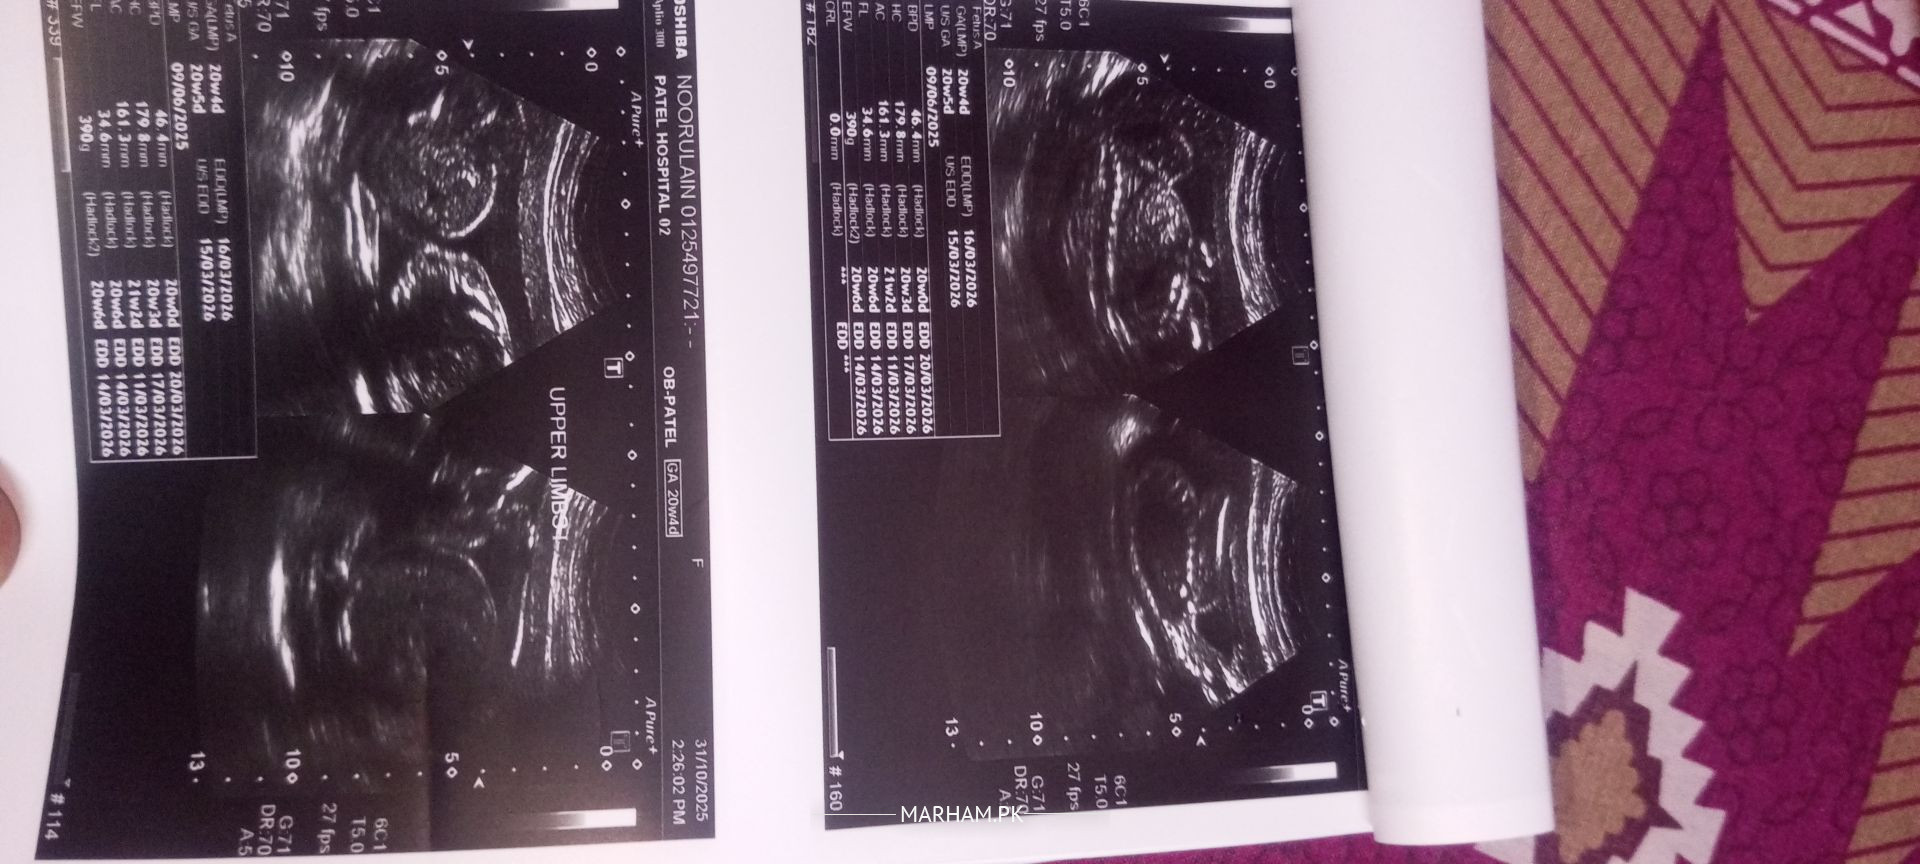

Attached in the anomaly scan report, I would request gynecologists to please comment Could I know baby's gender?

Salam Alaikum overall anomaly scan is normal but there is accumulation of urine in kidneys of fetus ,concern you gynaecologist need proper follow up.

Would it be resolved at later stages (weeks)?

It can resolve later in pregnancy you need serial ultrasound monitoring for this condition .